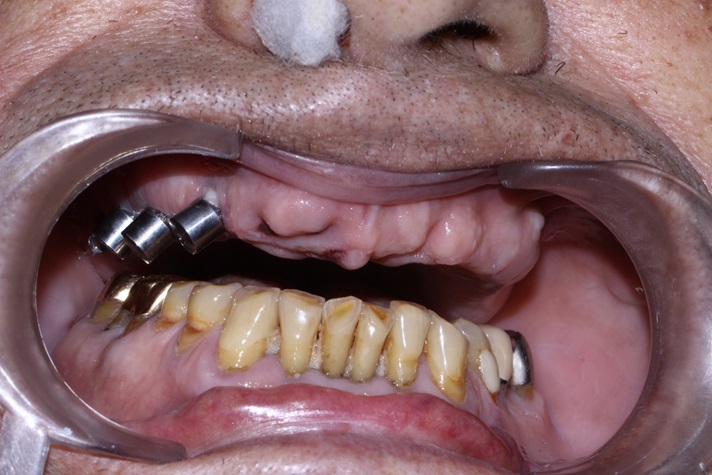

Tall and Tilted Pin Hole Immediate Loading ( TTPHIL) is a modern and most reliable technique for dental implantation. The special feature of such method is that dentist combine long and wide implants with bi-cortical support bone.

The All on 6 and All on 4 technique apply that method of implants placement.

This case report show the successful All on 6 dental implantation using Alpha Dent implants.